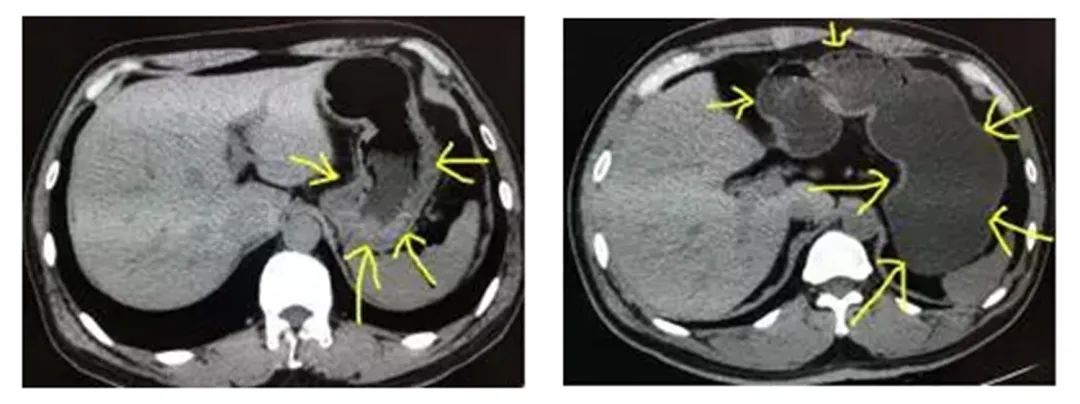

图中黄色箭头指的就是胃,左图是没有喝水,没有充盈好的胃,可以看到箭头指的胃壁明显是厚的,而正常的胃壁也是厚的,如果里面隐藏长着东西,刚好胃壁这里有个小胃癌,那就很可能没办法看清楚,导致漏诊。

右图图像的胃肠道准备就做得很好,可以看到胃壁被填充成薄薄的一层了,如果长东西胃壁异常增厚,就可以一目了然,做出诊断。